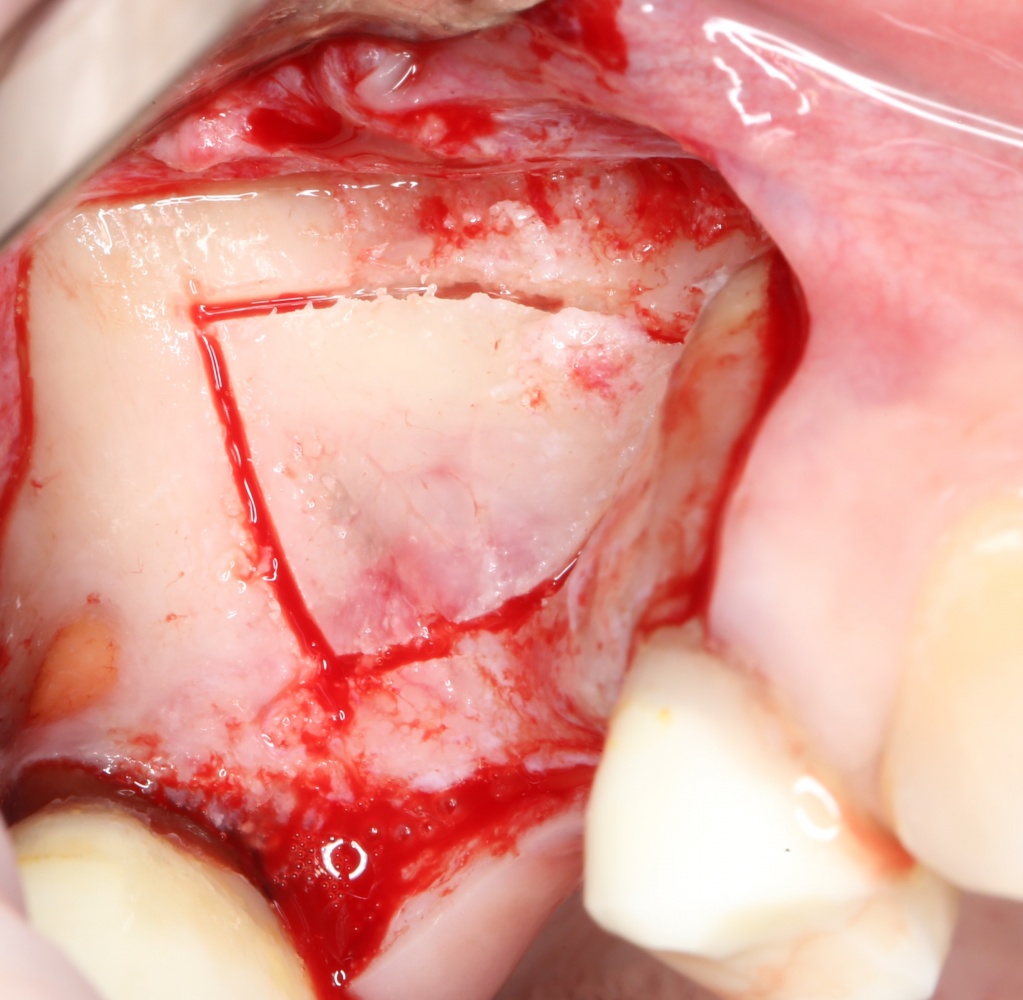

Простой синуслифтинг. Часть I.